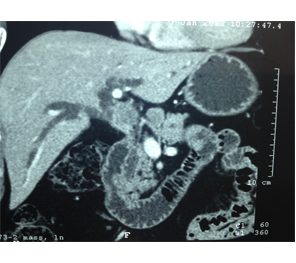

HCC in a non cirrhotic liver

Large HCC in seg 2 & 3

Large HCC in seg 2&3